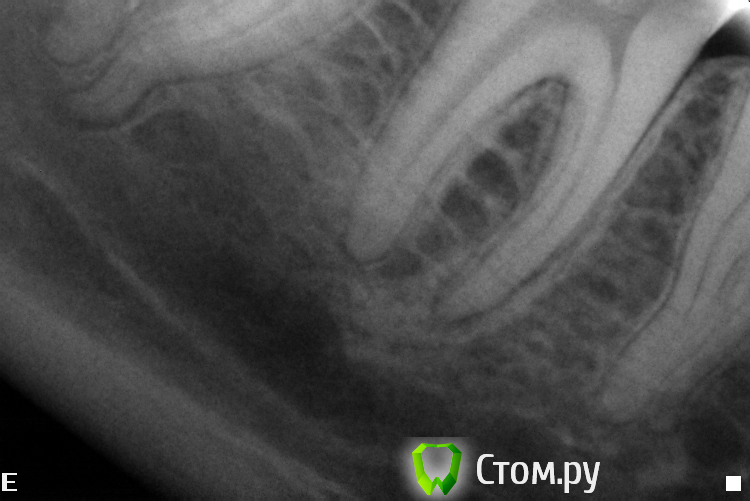

Slaggy Опубликовано 2 октября, 2014 Автор Поделиться Опубликовано 2 октября, 2014 Почётно ! Как извлекали ? Сколько по времени ? Почему без коффердама ? Руками, соник, ультрасоник, бино 3.5Гемор, если чесно, но я, вопреки мнению пациента полез в зуб на поиски МВ2, пришлось сделать все, чтоб исправить.4 посещения:1 - посмотрел на лунку, сказал что не она, полез в зуб, нашел мв2, снимок (не все удается скопировать, а база очень ограничена - неудачная программка стоит), непонравился МВ, прошел и снимок2 - прошел МВ2, сломал в МВ желтый Н, наломал кучу в МВ3 - достал все кроме первого (в клинике нет внутриканальных инструментов, решил принести свой эндочак и u-files)4 - принес свой чак, достал последний и запломбировал МВ и пломба. В клинике общий эндоинструмент, поэтому ломаки бывают непредсказуемые.В свой первый день тут я выкинул все. Весь ручной и машинный инструментарий - весь повитый был.Сейчас начальство стало прислушиваться (я ж их блатных лечу), скоро налажу все. 2 Ссылка на комментарий

Slaggy Опубликовано 2 октября, 2014 Автор Поделиться Опубликовано 2 октября, 2014 (изменено) Ну почётно,что тут скажешь. Вы сами знаете, что подтянуть. Но зуб я всё -таки покрыл бы в итоге,когда дойдёт до протезирования. Да все тянуть надо, при этом 10-12 пациентов в день.Сегодня 3 эндотрупа моляров работаны, Один свежий пульпит , 3 сдачи/фиксации, 1 съемник и 1 профгигиена. Про эндотрупы: ушел под кальцийКстати, это еще приличные снимки. обычно любуюсь апикальной третью корней ))))Тут в резорцинке косяк произошел. Видимо при конденсации проскочила гутта ((( расстроился.Но её хирург протежировал, Поговорю с ним, если апико сделает, то я не полезу. Изменено 2 октября, 2014 пользователем Slaggy 1 Ссылка на комментарий